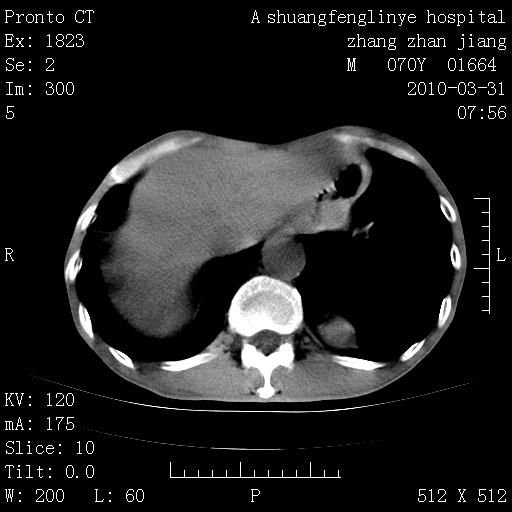

双上肺继发型tb并左上空洞形成,主动脉冠脉钙化。

1)两肺上叶继发性肺结核并左肺上叶空洞形成。2)冠状动脉及主动脉钙化。